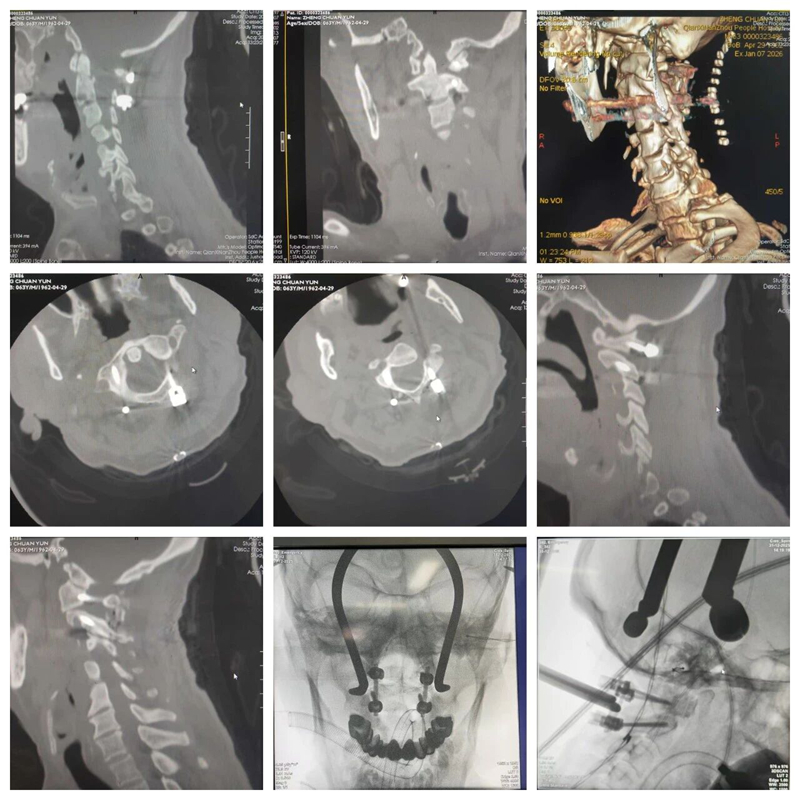

术前影像

患者郑某某在驾驶三轮机动车时不慎从约3米高处坠落,当即出现全身多处剧痛,尤以颈部严重,伴四肢活动受限及全身麻木。伤后三小时内由120紧急送入我院急诊外科。入院时患者神志清楚,但精神状况差,并出现呼吸急促、血氧饱和度明显下降等危险征象。经完善颈椎CT、MRI等影像学检查,提示为:枢椎齿状突骨折,寰椎后脱位,上颈髓及延髓挫伤。诊断为:枢椎齿状突骨折后脱位,脊髓损伤 Frankel A级,病情十分危重。

术后CT 复查

目前,患者枢椎齿状突骨折、脱位达完全解剖复位,寰枢椎螺钉固定理想,上颈髓卡压完全解除,脊髓及延髓水肿逐渐消退,患者各项生命征稳定,四肢肌力明显恢复,大小便可自解,并可佩戴头颈胸支具维持坐位,在他人搀扶下实现站立。这一恢复成效标志着该例极高难度上颈椎损伤救治取得了阶段性重大成功。